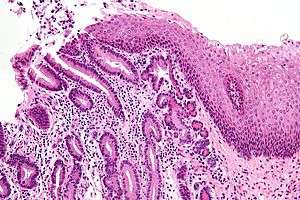

| Micrograph of a gastro-esophageal junction with pancreatic acinar metaplasia. The esophageal mucosa (stratified squamous epithelium) is seen on the right. The gastric mucosa (simple columnar epithelium) is seen on the left. The metaplastic epithelium is at the junction (center of image) and has an intensely eosinophilic (bright pink) cytoplasm. H&E stain. | |